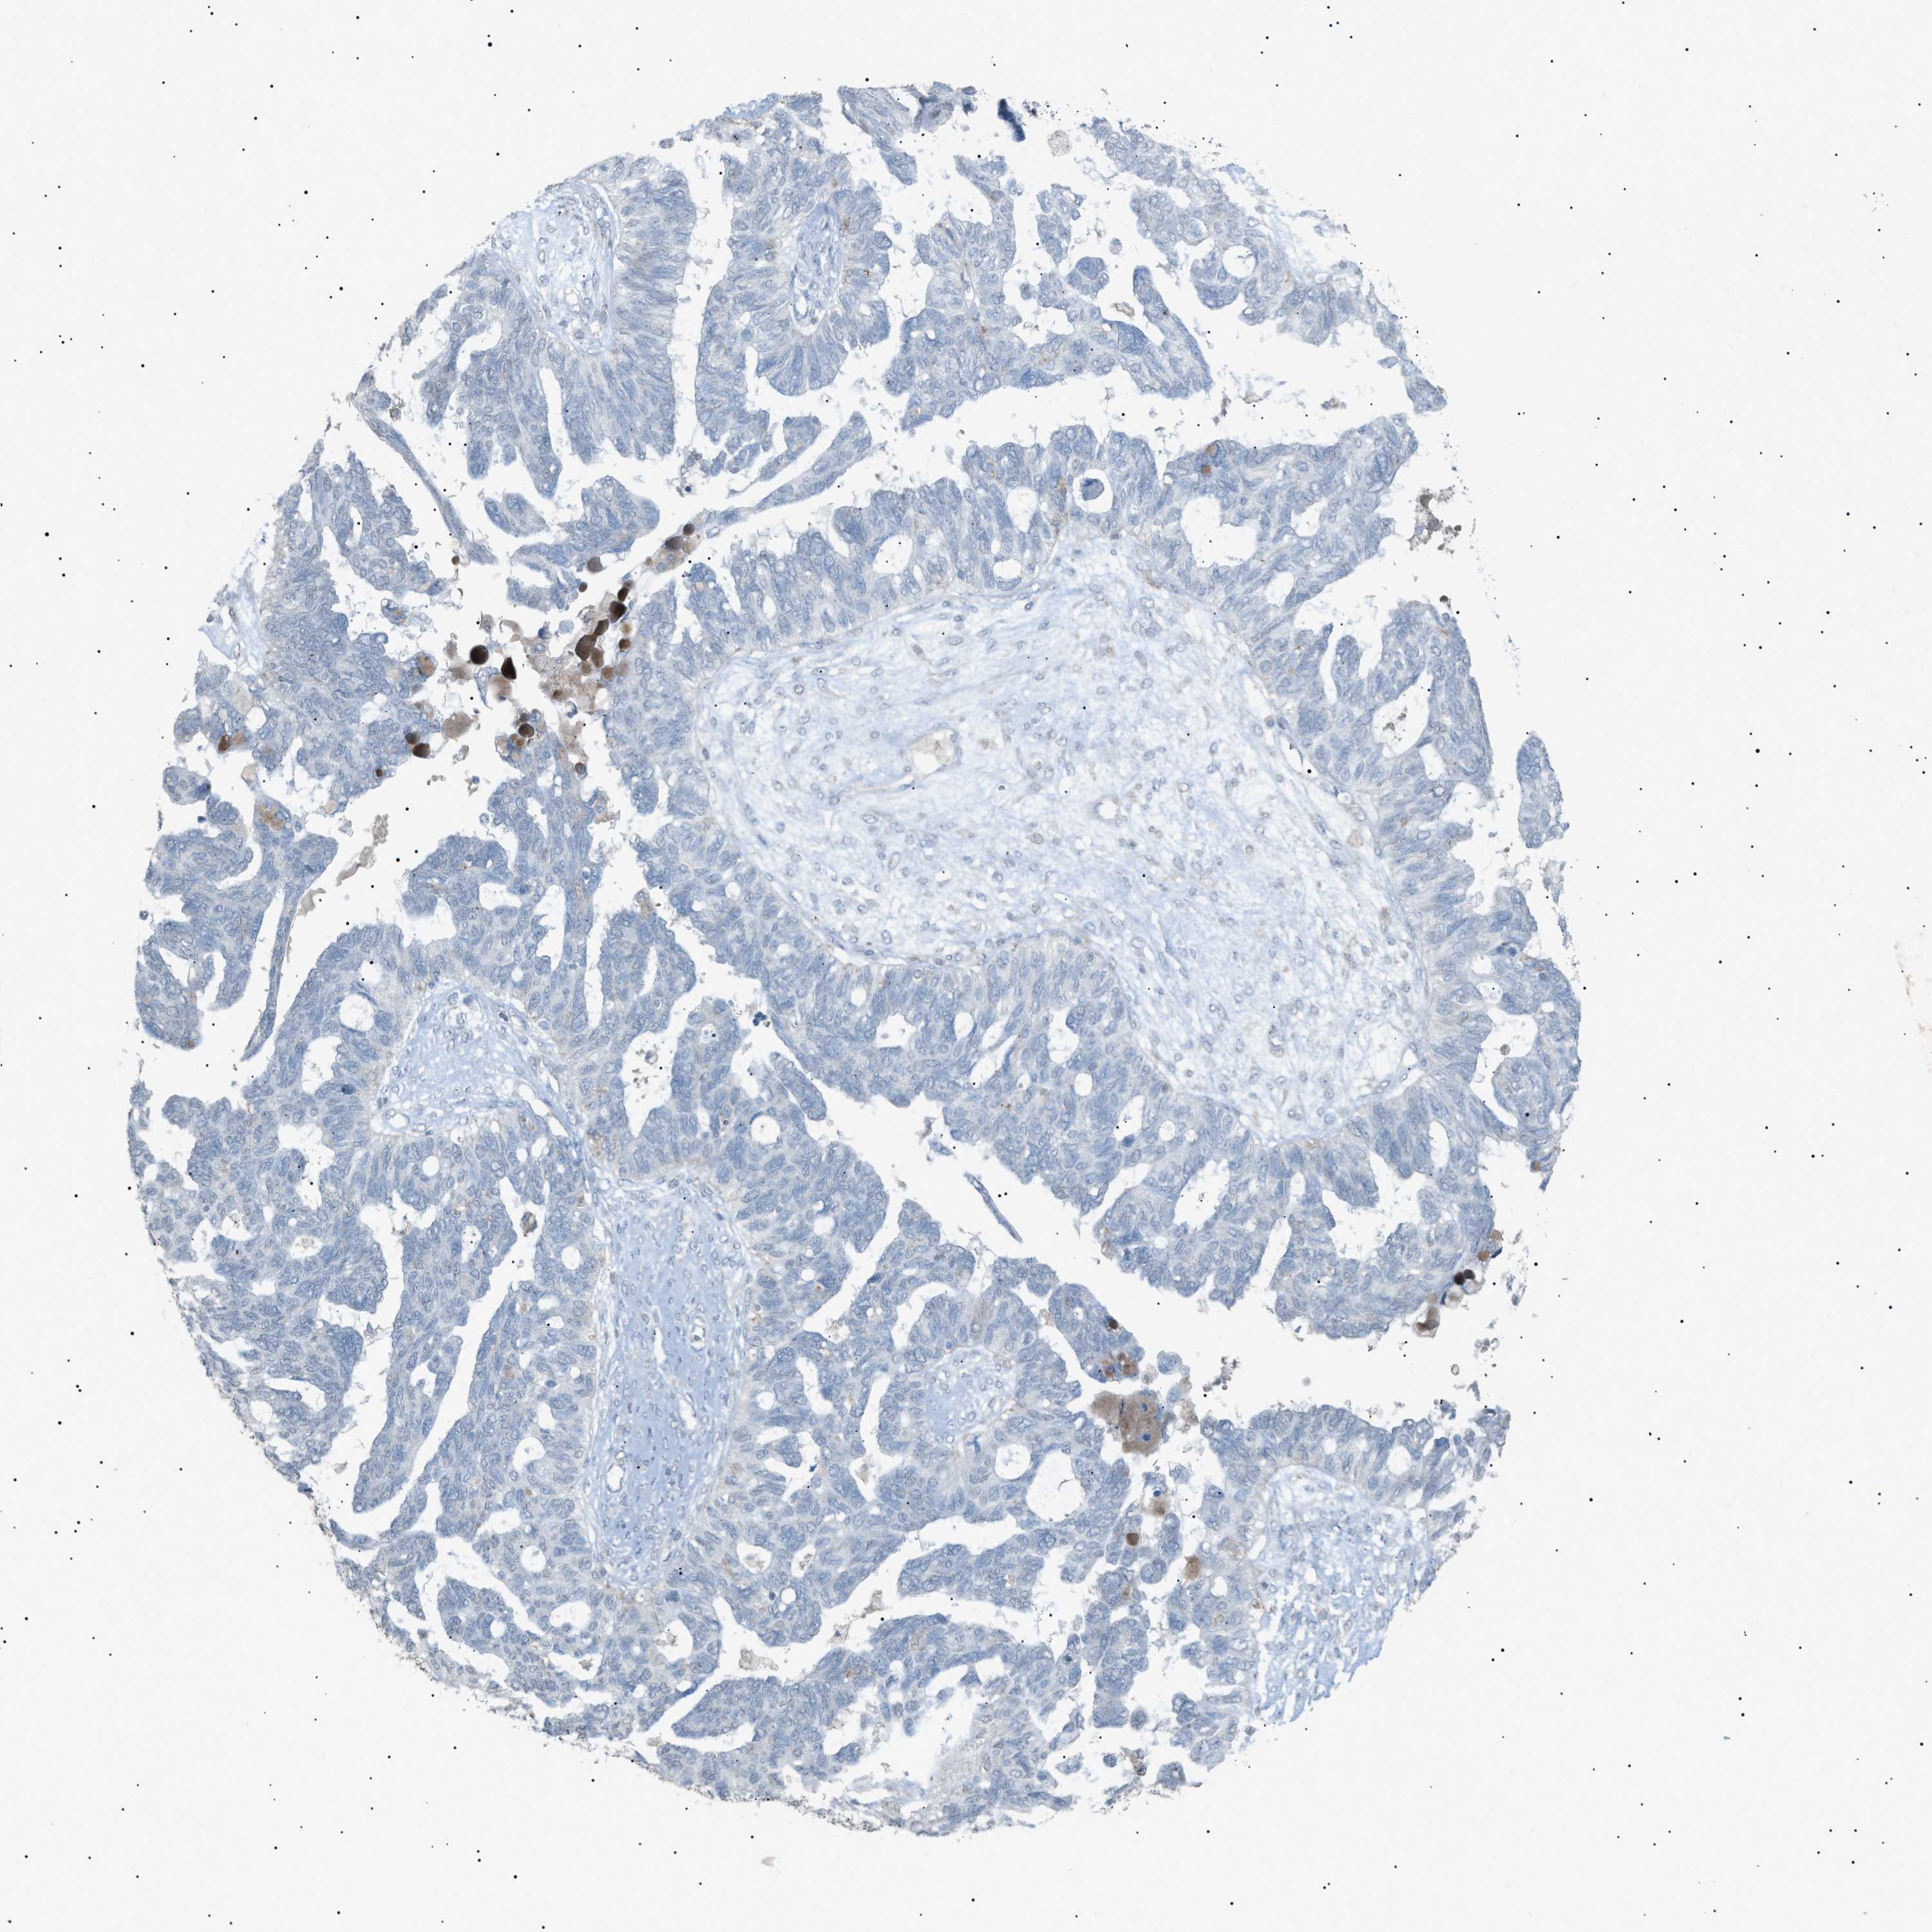

OVARIAN CANCER - Protein expressioni

A mouse-over function shows sample information and annotation data. Click on an image to view it in a full screen mode. Samples can be filtered based on level of antibody staining by selecting one or several of the following categories: high, medium, low and not detected. The assay and annotation is described here.

Note that samples used for immunohistochemistry by the Human Protein Atlas do not correspond to samples in the TCGA dataset.

Antibody stainingi

Antibody staining in the annotated cell types in the current human tissue is reported as not detected, low, medium, or high, based on conventional immunohistochemistry profiling in selected tissues. This score is based on the combination of the staining intensity and fraction of stained cells.

Each image is clickable and will lead to virtual microscopy that enables deeper exploration of all samples and also displays staining intensity scores, fraction scores and subcellular localization as well as patient and tissue information for each sample.

Antibody HPA001198

Antibody HPA002028

Antibody CAB016689

Antibody CAB080300

Cystadenocarcinoma, mucinous, NOS

Carcinoma, endometroid

Cystadenocarcinoma, serous, NOS

Carcinoma, NOS